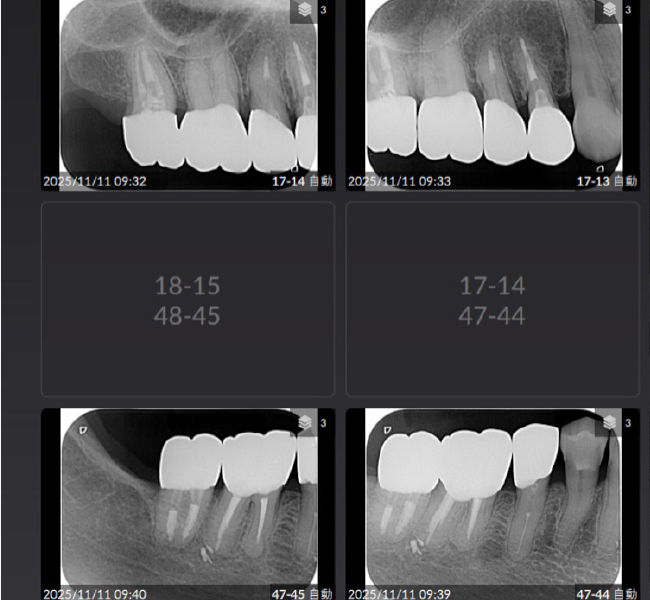

治療前